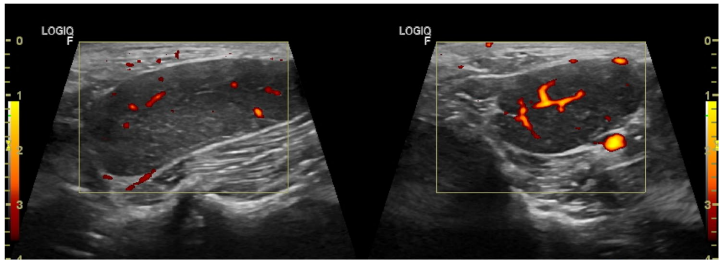

本刊推荐:针对犬类全身性淋巴结病变易误诊为淋巴瘤的问题,研究人员通过一例迷你雪纳瑞犬的临床案例,开展鸟分枝杆菌复合体(MAC)感染模拟恶性肿瘤的鉴别诊断研究。通过细胞学染色、分子鉴定(GenoType Mycobacterium CM)及药敏测试,确诊MAC感染并调整治疗方案(克拉霉素替代利福平)。结果强调齐尔-尼尔森染色在细胞学检查中的关键作用,揭示迷你雪纳瑞犬可能存在CARD9基因相关的免疫缺陷易感性。该研究为罕见人兽共患病的精准诊疗提供重要参考,发表于《BMC Veterinary Research》。